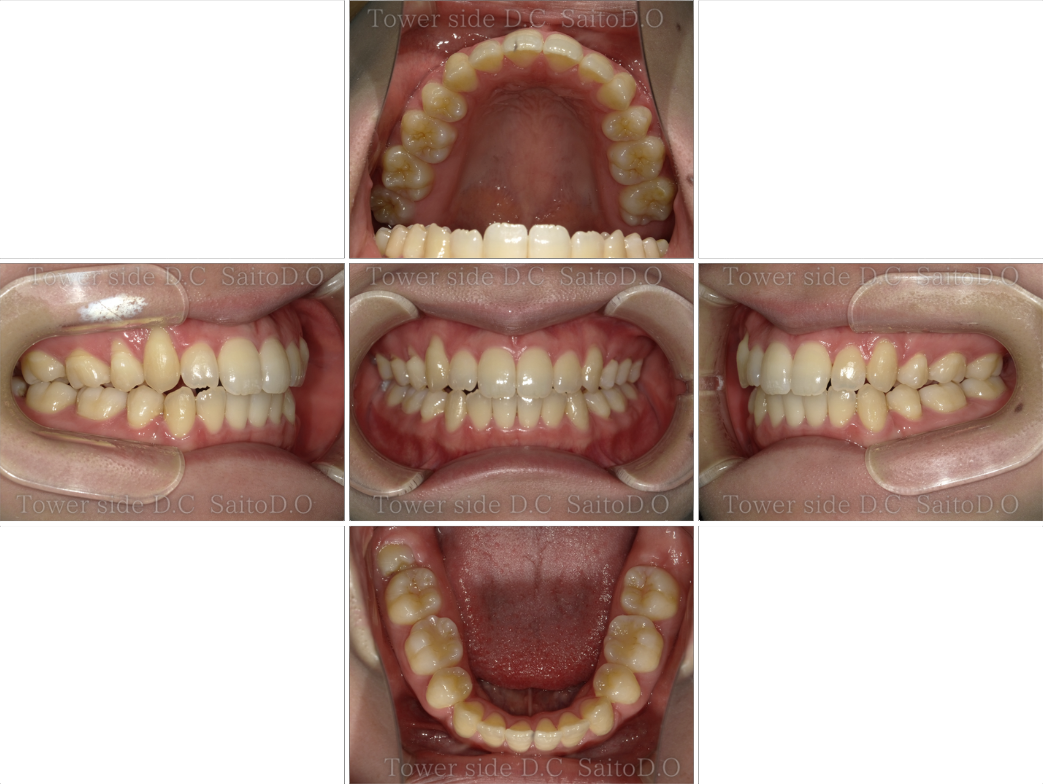

症例10CASE 10

|20代歳(女性)|

ワイヤー インビザライン症例

症例(施術前)

症例(施術後)

主訴 上前歯が出ている、上下前歯がガタガタが気になる

状況

• 上顎前歯前突

• 下顎前歯叢生

• 過蓋咬合

治療費 968,000円(税込)(自由診療)

治療期間 2年3ヶ月

治療内容 14.24を抜歯し、ワイヤー部分矯正で抜歯スペースを閉鎖後、マウスピース矯正を使用して臼歯部や前歯の方向を正しい向きに改善。歯並び、過蓋咬合、臼歯部噛み合わせは改善されその後保定装置(リテーナー)を使用し安定している。